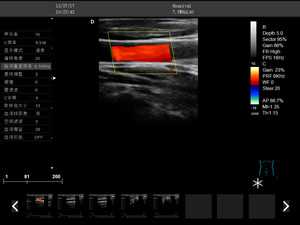

DW-F3

彩色多普勒

全數(shù)字成像技術(shù)

2.彩色多普勒速度模式

3.能量多普勒模式

4.方向彩色能量多普勒模式

5.脈沖頻譜多普勒模式

6.三同步模式

7.分屏實(shí)時(shí)顯示模式